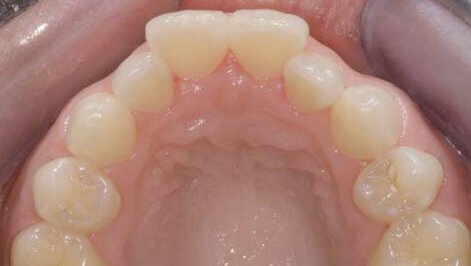

Inicijalnim pregledom pre izrade okluzalnih fotografija već je bilo sasvim jasno da bi za izradu ljuspica bila neophodna ekstenzivna preparacija gornjih centralnih sekutića. Preparacija bi sezala duboko u dentin, i nije bila isključena mogućnost da bi bio neophodan čak i elektivni endodontski tretman. Što se lateralnih sekutića tiče, oni nisu zahtevali opsežniju preparaciju za izradu ljuspica, ali bi njihov profil bio veoma loš, što bi stvaralo neprirodni izgled svih nadoknada, a takođe bi i postojao rizik od nastanka parodontopatije u kasnijem životnom dobu. Umesto svega toga, korigovanje položaja zuba sprovedeno je pomoću Inman Aligner-a u vremenskom periodu od deset nedelja. Terapijske faze sprovedene kod ove pacijentkinje detaljno su opisane dalje u tekstu.

Sačinjene su digitalne fotografije korišćenjem BACD sistema, a stepen teskobe prednjih zuba određen je elektronskim putem, što je moglo biti sprovedeno i analizom studijskih modela. Odredili smo idealne dimenzije luka i ove vrednosti oduzeli od zbira mezio-distalnih širina zuba, čiji položaj smo planirali da korigujemo3. Rezultati su pokazali da je vrednost teskobe, odnosno prostora koji zapravo nedostaje samo 1,6 mm. Ovo je bilo značajno manje od onoga što se moglo očekivati; razlog za ovakav nalaz jeste činjenica da su lateralni sekutići bili retroklinirani, luk je ekspandiran i na taj način je dobijen prostor.

Posmatranjem fotografija bilo je očigledno da pored evidentne teskobe postoji i nešto manje uočljiva nepravilna abrazija zuba. Bilo je veoma važno skrenuti pacijentkinji pažnju na postojanje ovih promena, jer će one postati izraženije kada dođe do korigovanja položaja zuba. Pacijentkinji je predložena izrada tri adhezivne restauracije na incizalnim ivicama zuba kod kojih je uočena abrazija. Pacijentkinja se odlučila za tretman Inman Aligner-om sa ugrađenim šrafom za širenje. Ovi šrafovi su veoma efikasni za dobijanje dodatnog prostora, u komplikovanijim kliničkim slučajevima, ali i u slučajevima kada se želi izbeći interproksimalna redukcija (IPR) stripovanjem.

Načinili smo okluzalne fotografije njenih prednjih zuba i na njima ucrtali količinu zubne supstance koja bi morala biti uklonjena ukoliko bismo se odlučili za izradu ljuspica koje bi imale odgovarajući estetski efekat. Pacijentkinji je odmah postalo jasno da korigovanje nepravilnog položaja njenih zuba nudi potencijalno bolji terapijski ishod. Njena klinička situacija bila je pogodna za korišćenje Inman Aligner-a, a kako je nedostatak prostora iznosio samo 2,5 mm, što je ukazivalo da tretman može biti sproveden brzo i jednostavno.

Analizom okluzalnih fotografija, pacijentkinji je objašnjeno u kojoj meri bi morao biti agresivan tretman ukoliko bi se zubi preparisali za izradu ljuspica. Shvatila je da njeni zubi zahtevaju korigovanje položaja pre nego što se donese odluka o sledećem koraku.